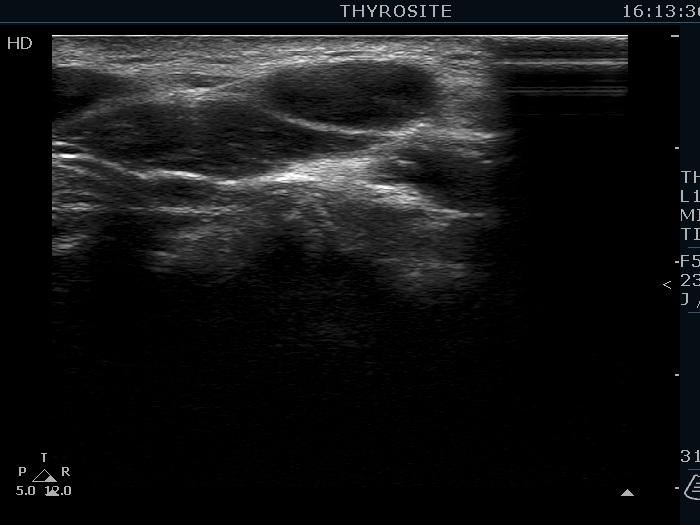

Ultrasonography. The thyroid was echonormal. There were several hypoechoic nodules in the left lobe. The middle one had back wall cystic figures. There were 3 or four discrete, deeply hypoechoic lesions above and lateral to the left lobe in the neck. One of them presented with a hilum-like figure while the others lacked hilum.

The lymph nodes had a non-typical presentation. They lacked a regular hilum.